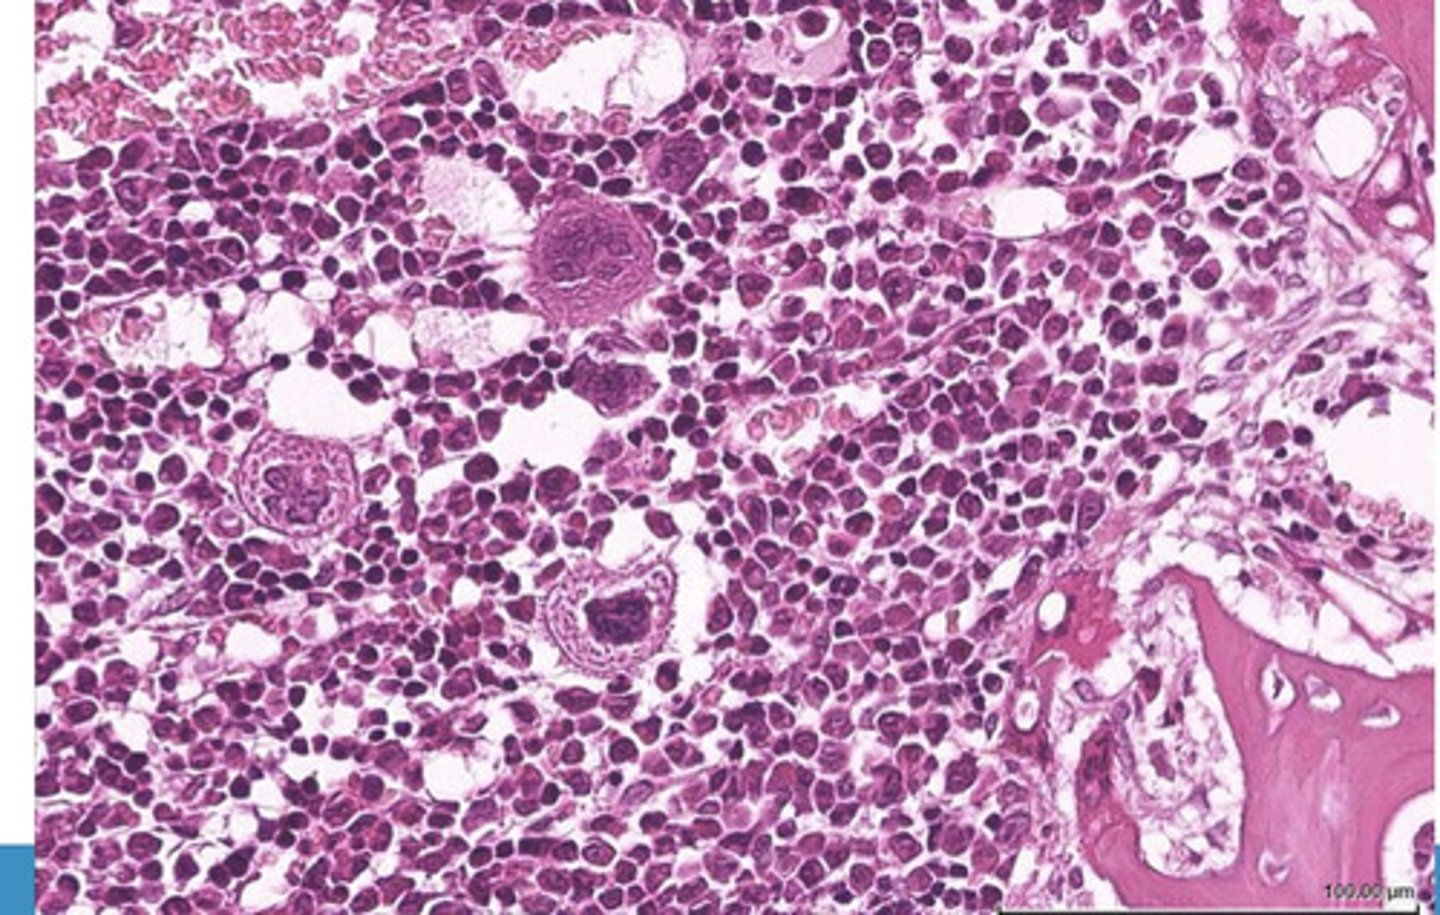

red bone marrow

what is this?

what are the components of the red bone marrow?